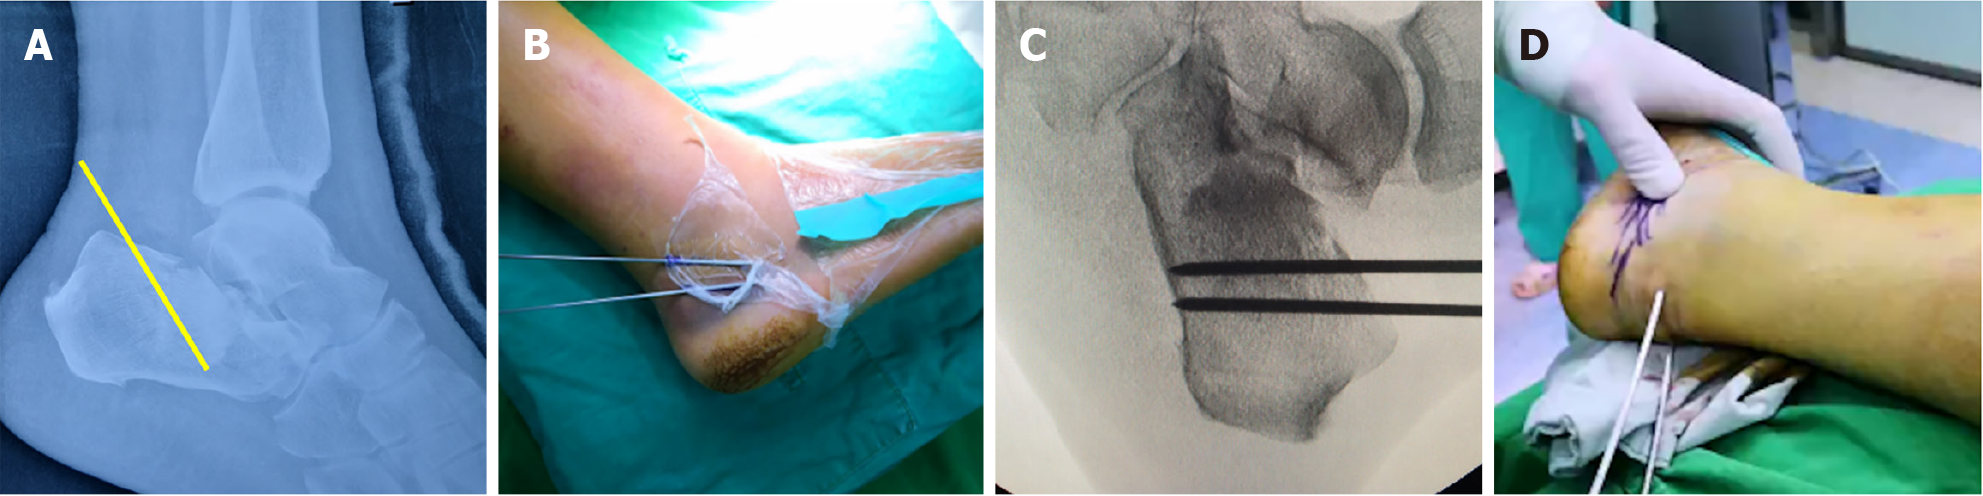

Figure 4 Intraoperative fluoroscopy demonstrating the reduction procedure and outcomes.

A: After prying reduction restored the normal Böhler’s angle, the Steinmann pin was used to engage the distal fracture fragment posterior-inferior to the calcaneal body for eversion reduction; B and C: With compression applied to both sides of the calcaneus, fluoroscopy confirmed satisfactory reduction. A 2.5 mm guide wire was then drilled from the posterior calcaneus in an anterior direction; D: Post-reduction photograph.